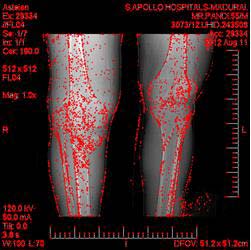

In the proposed work, two various types of image processing techniques are applied for the input (Big Data) as shown in the Fig. 3. The first technique is the combination Grayscale and Sobel edge detection. The second technique is the combination of Gaussian Blur and Fast Corner detection method. The Grayscale conversion is the best method to convert the original image into Black and White image and Sobel edge detection is the method of detecting the edges of the images.

Gaussian Blur is the best blurring technique ever, used here to blur the input image. Finally the Fast Corner Detection technique, since that is the best technique. After the completion of both the processing, the data is then transferred to the next level of Matching called SAD matching. Then the integration of the intermediate data is done to recognize the output.

The Harris corner detection is used in case when there is a correlation in the threshold of data. A detection method which could give a better result than the Harris corner is, Fast corner_9 which is shown in Fig. 4. Fast corner_9 has been applied in the proposed work, to fine tune the result than the Harris corner, Susan, zheng and harr [9] methods.

Fig 5 shows the result of the Fast Corner method. In this figure, the sharp edges and the damaged parts are pointed out sharply. The red mark shows the infected corners. When compared with the Harris corner method in the existing work [2], this is proved to be the best corner detection. The application of the two image processing techniques, gives the expected result. The main advantage during the execution was, the output of the data is marked with better quality and there is the usage of Fast corner_9 method to detect the corners of the image. While comparing with existing, proposed Fast corner_9 method shows the corner more clearly. During the comparison, it has been proved that, the method applied in the proposed algorithm works better than the existing. Whatever the size or format of images may be, the result will be produced in the pre defined format. The result occupies less space when compared with the size of the input for storing.